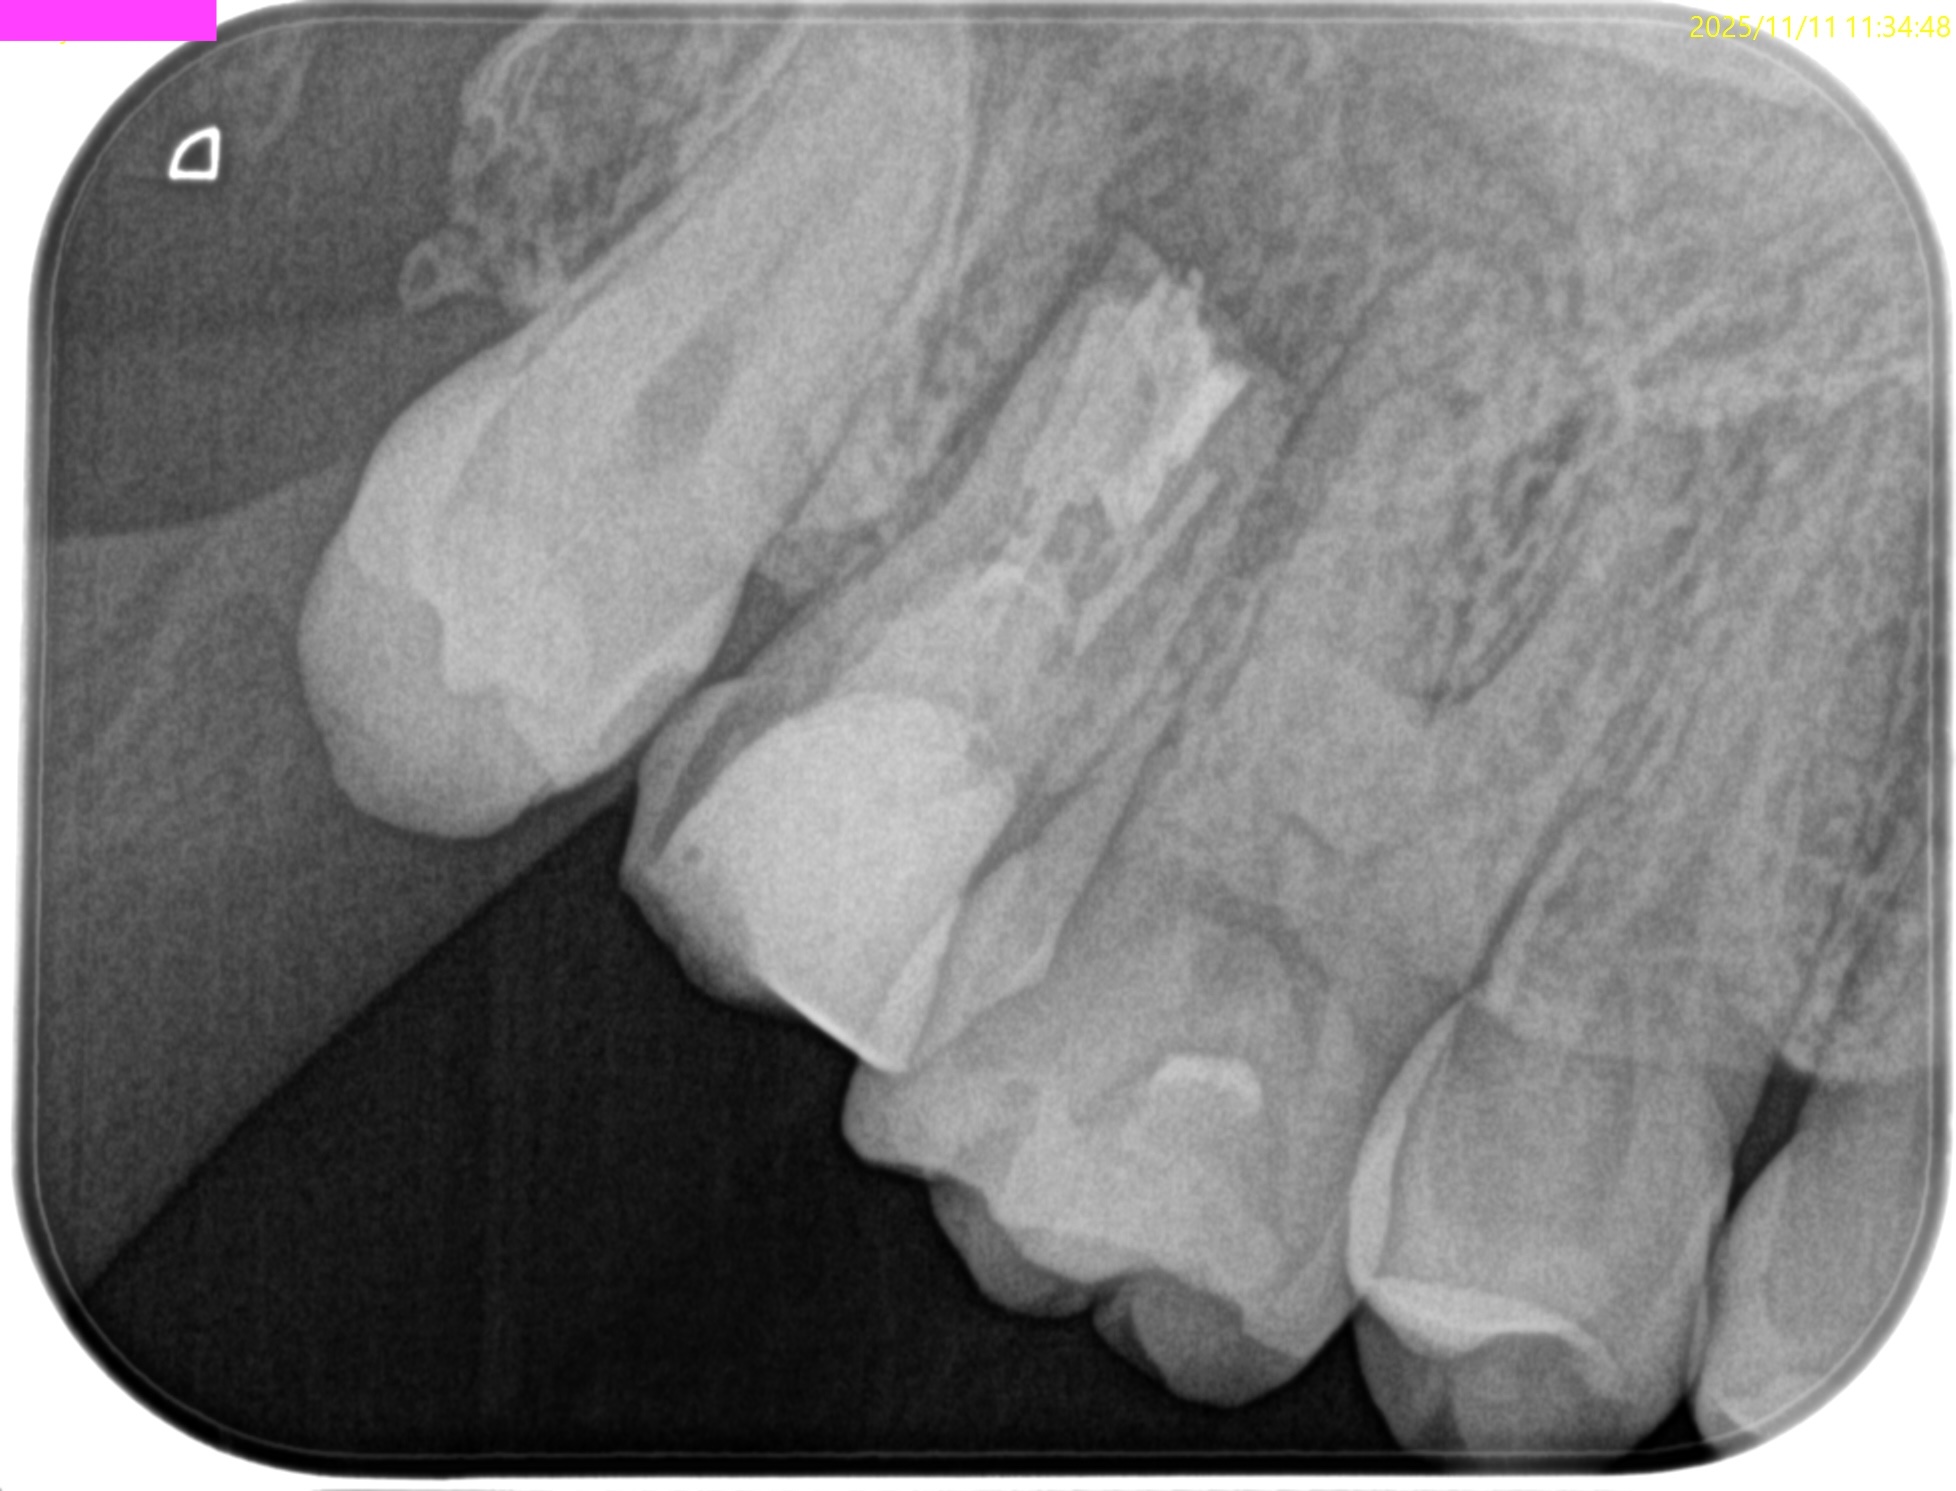

PA(2025.11.11)

CBCT(2025.11.11)

MB

DB

P

根管は石灰化&すでに拡大済みであるので、再根管治療ではなく外科治療、つまり、Intentional Replantationの適応症である。